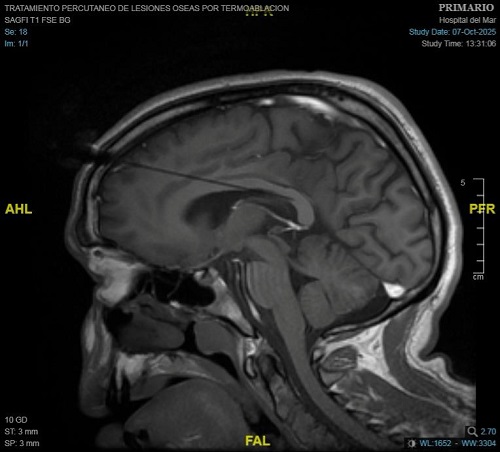

En el primer caso tratado en el Hospital del Mar, el pasado 7 de octubre, el equipo liderado por el Dr. Carlo Marras, jefe del Servicio de Neurocirugía, junto a la Dra. Nazaret Infante, médica adjunta del mismo servicio, trataron a un paciente con un tipo de epilepsia resistente al tratamiento farmacológico y que no era tributario de una cirugía curativa. Después de un proceso de planificación con imágenes 3D junto al equipo de la Unidad de Epilepsia, encabezado por el Dr. Rodrigo Rocamora, se seleccionó el área del cuerpo calloso del cerebro a tratar para interrumpir la comunicación entre los dos hemisferios cerebrales.

Para ello, con la ayuda de un sistema robótico, se colocan de dos a tres sondas láser a través de accesos milimétricos en el cráneo que servirán, con monitorización constante de imágenes de resonancia magnética, para realizar la intervención y obtener el resultado esperado. Gracias a las altas temperaturas que consigue alcanzar el láser, se actúa sobre la zona concreta del cuerpo calloso seleccionada sin afectar las zonas del cerebro circundantes. Así se logra "una lesión muy localizada", explica el Dr. Carlo Marras. En todo momento se controla la temperatura del láser para evitar afectar otras zonas del cerebro.